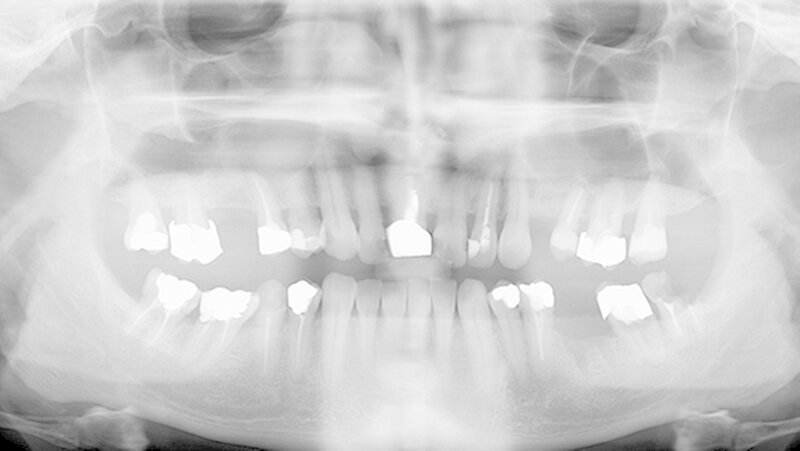

Oralchirurg Marcus Stoetzer arbeitete drei Monate lang im Feldlager der Bundeswehr in Mazar e Sharif - insgesamt behandelte er in Afghanistan 298 Soldaten. Die Bilder zeigen, aus welchem Grund sie zu ihm kamen.